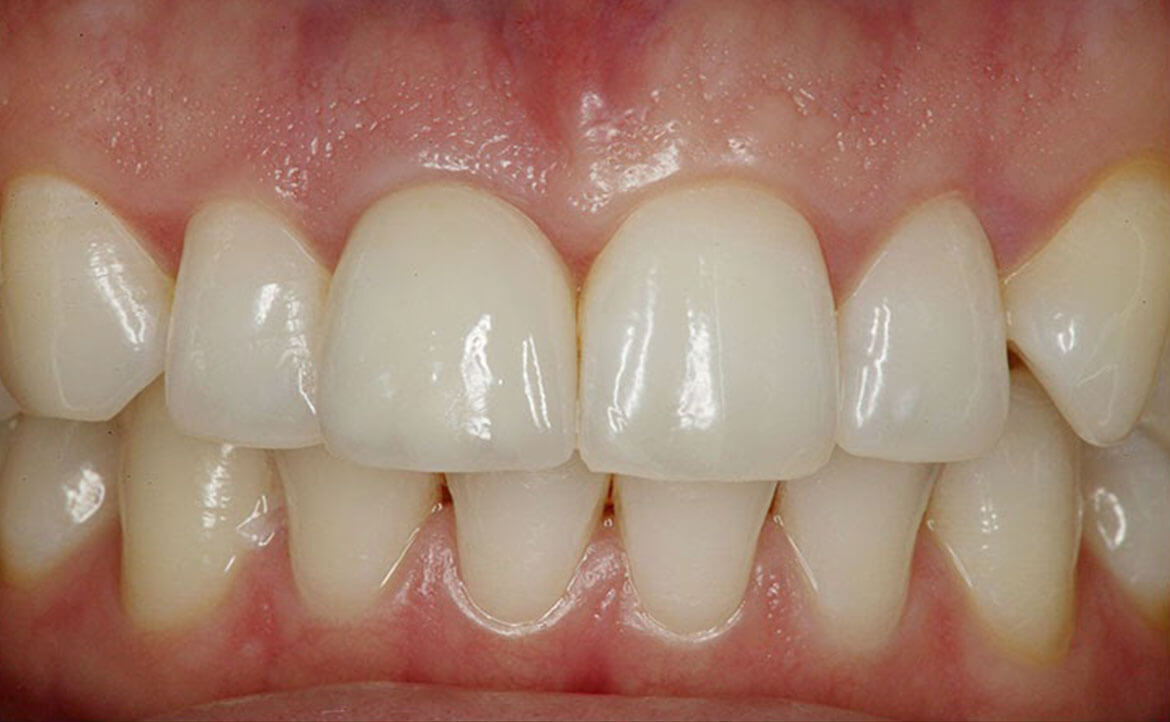

Puntea dentară este cea mai căutată soluție de umplere a spațiilor lipsă a danturii. Asta pentru că timpul de realizare este minim. Puntea este fixată pe dinții învecinați care, pentru o susținere mai bună, inițial sunt șlefuiți. Odată aplicată dantura capătă un aspect estetic natural și, dacă este întreținută corespunzător, are o durată de viață îndelungată.

Pe lângă restabilirea estetică a danturii, puntea dentară împiedică complicațiile care pot apărea de pe urma lipsei unui dinte. Odată aplicată va îndeplini procesul normal de masticație și va îmbunătăți funcția fonetică.